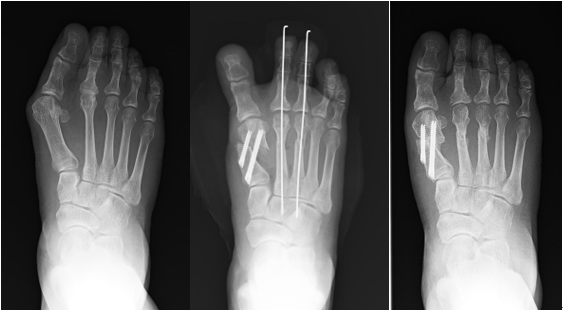

最も多い手術は、低侵襲手技での第1中足骨遠位骨切り術および第2・3中足骨短縮骨切り術です。小さい皮膚切開で第1中足骨を骨切りし、骨の形を変化させ、Screwで固定します。第2・3中足骨は短縮させて、ゆびの先からワイヤーを留置しておきます。外反母趾が超重度な症例や中足骨の根元の関節が痛んでいる症例では、関節固定術が検討されます。

術前 術直後 術後半年

入院期間は、4日~2週間程度になります。術後4~6週間程度は特別な靴を使用し、手術した部分に負荷をかけないように歩いていただきます。

手術の方法によっては、ワイヤーが足のゆびの先から出ていますので、術後4週でワイヤーを外来で抜きます。術後8週程度から通常歩行を許可しています。